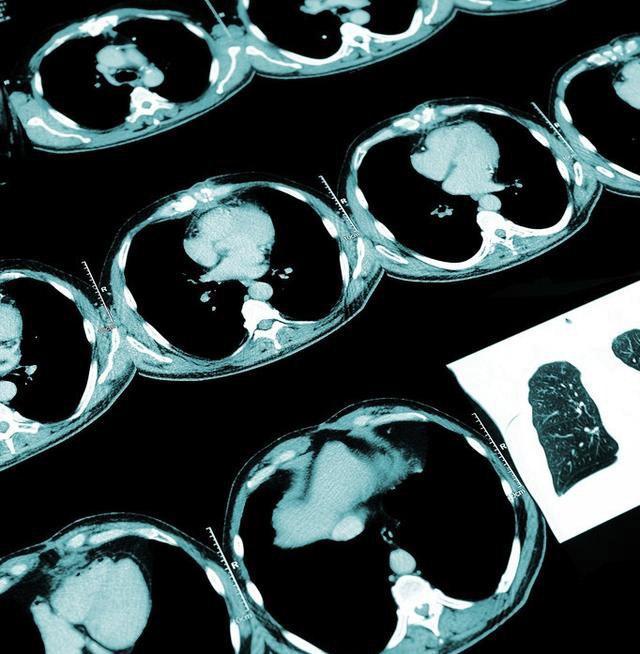

胸部CT则可以准确的发现1mm以上的病灶,并可以清除的反应病灶的大小,密度,周围是否有毛刺,是否影响到胸膜等情况和特征,对于判断其良恶性有很大的帮助,而且如果需要做手术切除,胸部CT提示必要的检查,有时候还需要在CT的定位下放金属丝标明结节的部位。